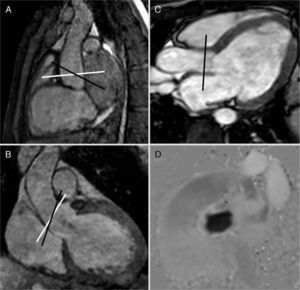

Steady-state images (3D-balanced FFE) in sagittal (A) and coronal (B) views; 2D-balanced image in a 3-chamber view (C) and phase image (D) of the aortic valve. The adequate planning takes place above the valve by placing the acquisition plane/view perpendicular to the direction of flow in two (2) orthogonal views (white lines in A and B). The 3-chamber view is used as the only reference and even though we can adequately see the valve the view will not be perpendicular to the flow (black lines in A and B), there will be an error of calculation in the speeds and therefore in the flow. Similarly this principle can be applied to all valves, vessels, and conduits.